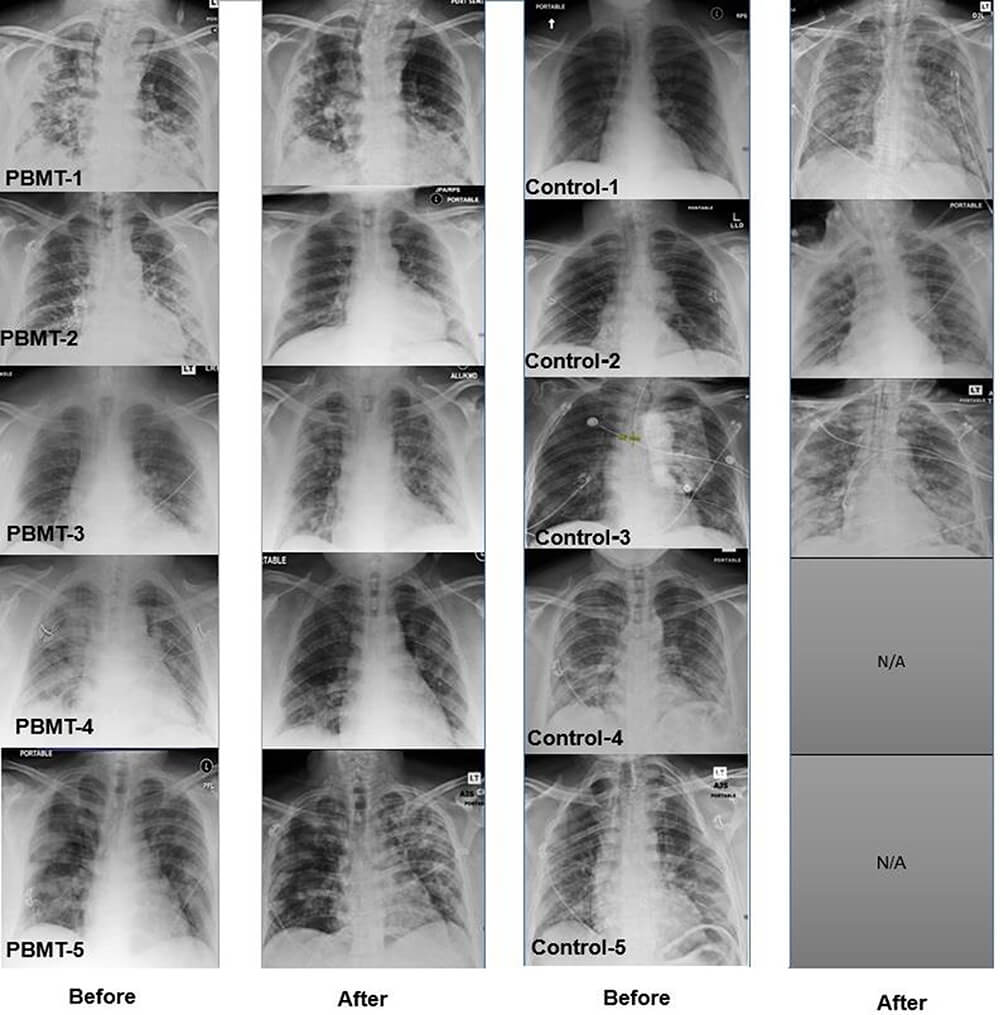

Figura 2. Radiografiile pulmonare demonstreaza imbunatatirea vizibila a imaginilor in grupul ce a beneficiat de PBMT si o inrautatire in grupul de control (prin consolidarea imaginilor de sticla mata) [1].